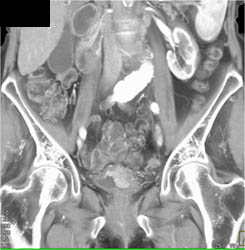

Bladder Cancer